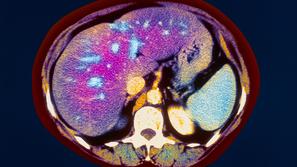

Zdravje Zamaščena jetra: Težava, ki jo ima 25 odstotkov Slovencev Nekoč je veljalo, da jo imajo le tisti, ki popijejo preveč alkohola.